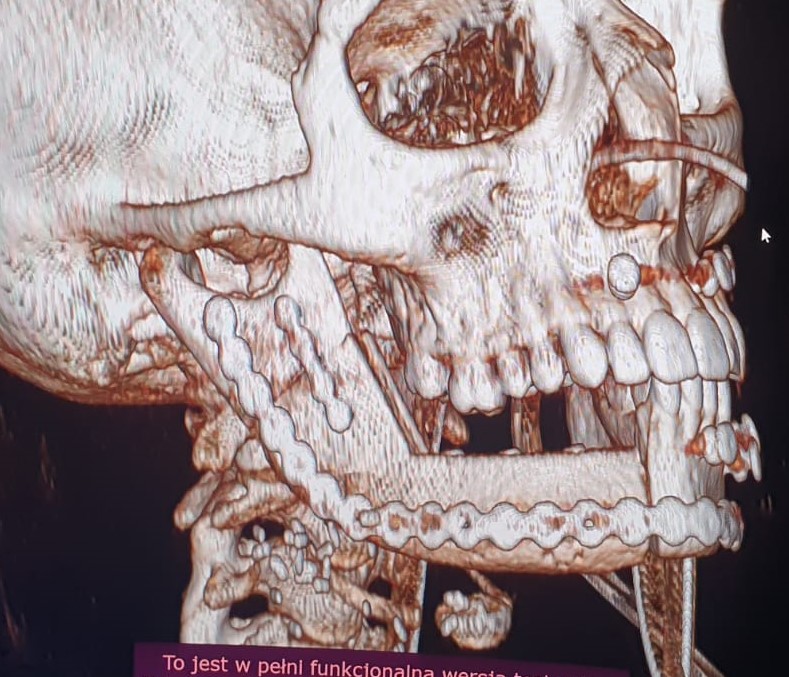

Pacjentka lat 15, zgłosiła się do poradni chirurgii szczękowo - twarzowej Szpitala Specjalistycznego im. L. Rydygiera w Krakowie z powodu rozległego guza trzonu, kąta i gałęzi żuchwy po stronie prawej. Na wykonanym zdjęciu ortopantomograficznym (OPG) uwidoczniono rozległy wielokomorowy ubytek kości żuchwy z całkowicie zatrzymanym zębem 46 w jego świetle oraz zepchnięciem zębów 47,48 w kierunku gałęzi żuchwy (Fig. 1.). W badaniu tomografii komputerowej uwidoczniono guz zniekształcający kość żuchwy po stronie prawej z jej rozdęciem i niszczeniem blaszki korowej od strony zewnętrznej oraz wewnętrznej (Fig. 2.). Wynik badania histopatologicznego pobranych wycinków z guza potwierdził rozpoznanie szkliwiaka (typ pęcherzykowo-akantomatyczny).

Fig. 2.Obraz w rekonstrukcji 3D badania tomografii komputerowej części twarzowej czaszki– widoczny guz powodujący znaczne zniekształcenie żuchwy po stronie prawej ze zniszczeniem blaszki korowej kości

W okresie pooperacyjnym nie stwierdzono powikłań w gojeniu ran pooperacynych. W wykonanych badaniach tomografii komputerowej części twarzowej czaszki (Fig. 21.) oraz OPG (Fig. 22.) potwierdzono poprawność rekonstrukcji żuchwy oraz prawidłową pozycję jednoczasowo założonych implantów. Po upływie 6 miesięcy od wykonanego zabiegu chirurgicznego i pełnym zrośnięciem się kikutów żuchwy z płatem mikrochirurgicznym z talerza kości biodrowej oraz osteointegracji implantów zębowych z przenoszonym fragmentem kostnym w chorej planowane są dalsze etapy leczenia implantoprotetycznego.

Fig. 21. Odtworzony fragment trzonu, kąta i gałęzi żuchwy po stronie prawej na rekonstrukcjach 3D kontrolnego badania tomografii komputerowej